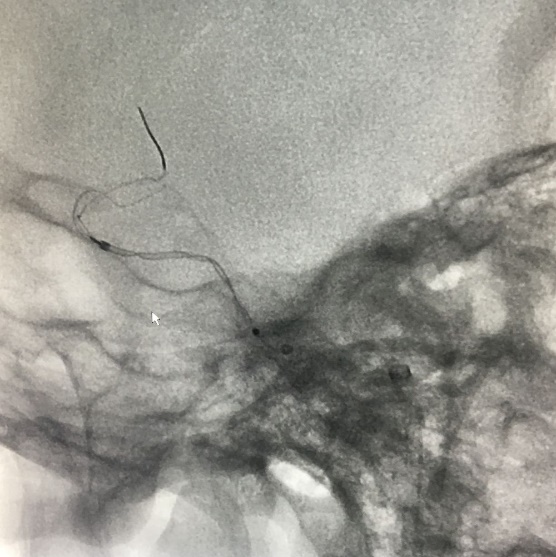

麻醉成功后,患者仰卧,常规消毒,铺巾, Seldinger法穿刺右侧股动脉,置入5F动脉鞘,置入5F造影管行右侧颈内动脉正侧位及3D造影后,更换6F长动脉鞘,6F中间导管在导丝引导下进入右侧颈动脉分叉端并固定。根据3D造影选择工作体位并放大做路图后,T-track微导管在微导丝引导下进入右侧大脑中动脉,经微导管送入4.0×45mm Tubridge®支架,观察 Marker位置后,于颈动脉分叉附近缓慢释放支架。

锚定后,整体回撤至合适位置后,通过张力释放法缓慢释放支架,直至支架完全打开。观察见支架贴壁良好,动脉瘤颈完全覆盖,遂完全释放支架。

全脑DSA正侧位造影示血流通畅。

动脉瘤内造影剂滞留,未填弹簧圈。行Xper CT,观察见支架完全打开,贴壁良好。术程顺利结束。